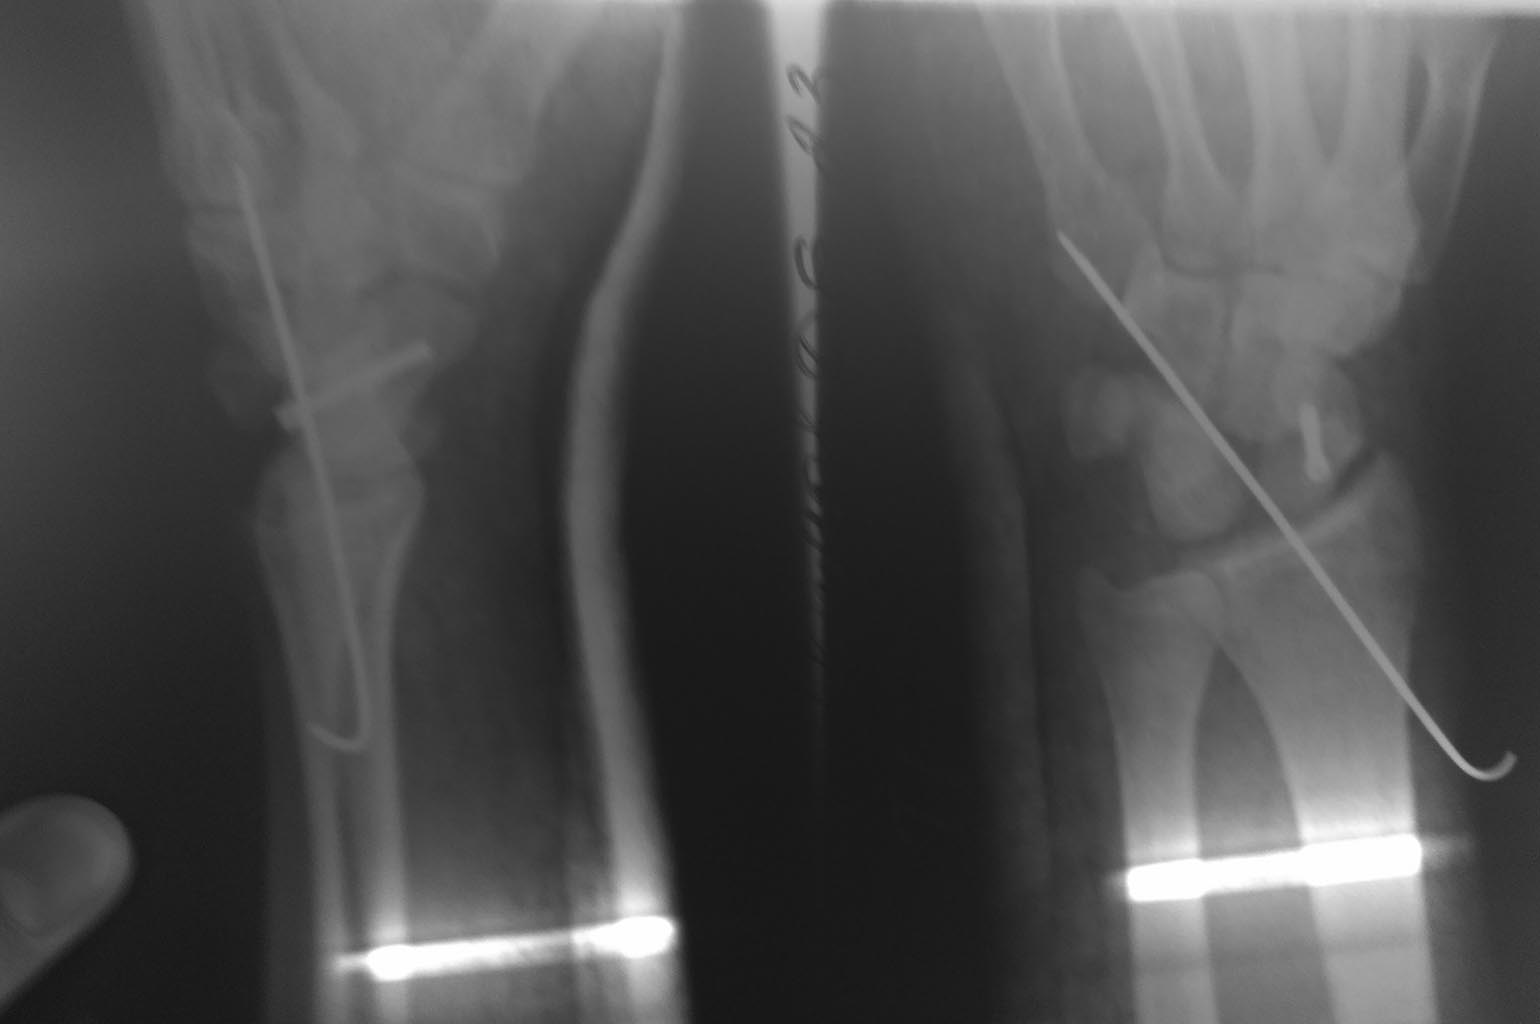

Перилунарный вывих

Здравствуйте коллеги, непонятный послеоперационный снимок. Вроде во время операции под эопом все было нормально.

Нет ли вывиха полулунной кости?